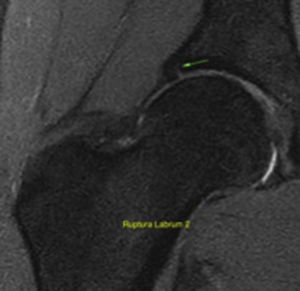

With regard to the type of FAI, there was a prevalence of 22.5% (n=18) of cam-type lesions, and of 1.3% of both pincer and mixed lesions (n=1) (Fig. 2). We found 33.8% labral lesions, and 18–8% (n=15) intrasubstance degeneration, 12.5% partial labral tear (n=10), and 2.5% complete labral tear (n=2) (Fig. 3). The prevalence of femoroacetabular cartilage lesions was 13.8% of the hips assessed, and we found acetabular cartilage lesions in 6.3% (n=5), this percentage was in turn distributed into 5% (n=4) with cartilage softening and oedema, and into 1.3% (n=1) with subchondral bone fissures >1.5 in diameter; 75% (n=6) had femoral cartilage lesions. An acetabular cyst was present in 5% (n=4) of the population. Chondrolabral damage was seen in 10% (n=8) and synovitis in 1.3% (n=1). Other findings were femoral head oedema in 5% (n=4), capsular or ligament thickening in 2.5% (n=2), coxa profunda in 17.5% (n=14) and labral or paralabral cyst in 1.3% (n=1). None of the players had cysts in the femoral head-neck union, round ligament impairment, retroversion or Os acetabuli.

To evaluate the labral lesions by MRI as the method of choice to identify soft tissue lesions around the hip, including the labrum and the cartilage, we used the following simplified classification: stage 0 normal, 1 intrasubstance degeneration, 2 partial tear, and 3 complete tear.